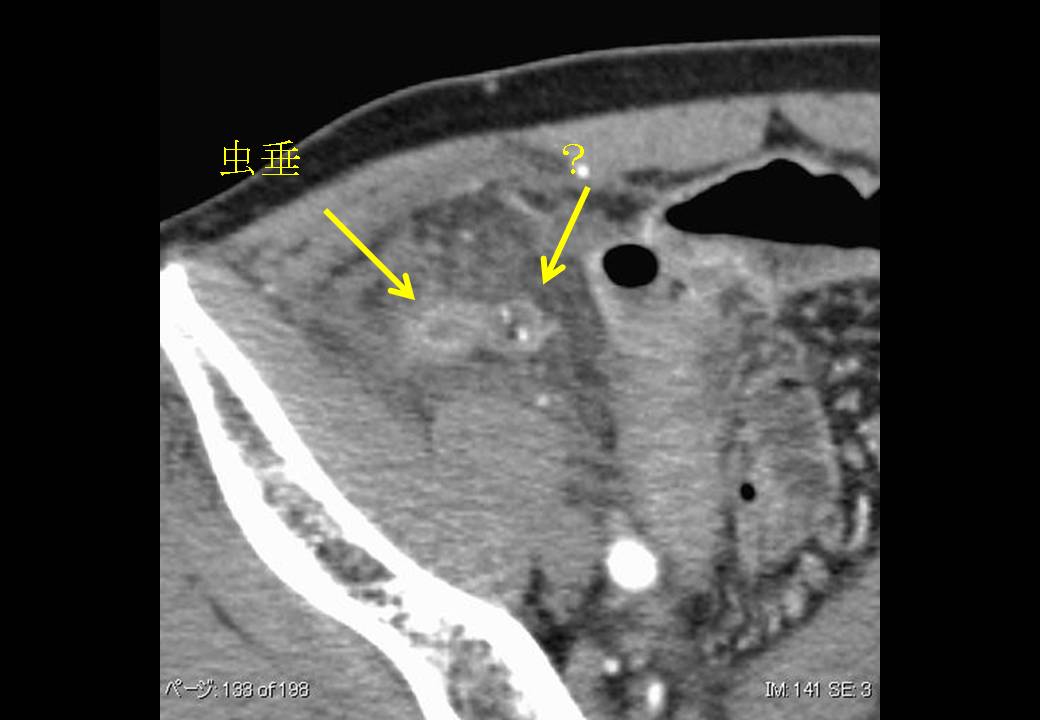

●日赤2 (清水先生) 59M 虫垂憩室炎